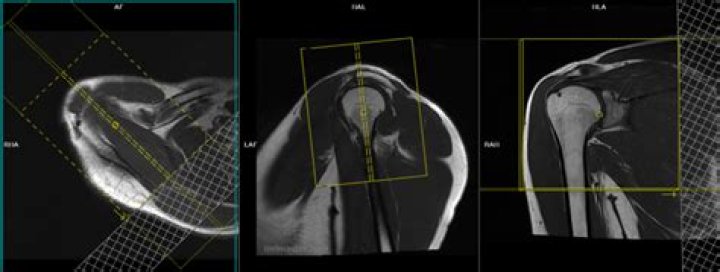

When examining using conventional MRI alone, T2-weighted images in the oblique coronal and oblique sagittal planes is the preferred technique for imaging the rotator cuff. Most radiologists have found that fat-suppressed, fast spin-echo, T2-weighted images are the most accurate for detecting rotator cuff tears.